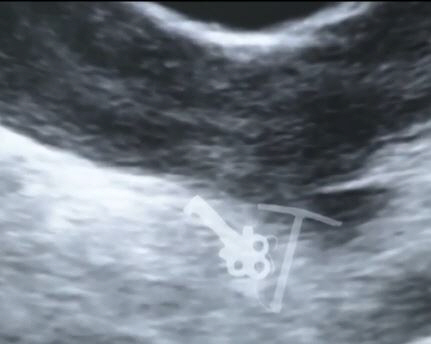

의료진이 수갑 열쇠의 행방을 묻자 커플은 여성의 배를 가리켰다. 둘이 파티를 즐기던 중 열쇠를 여성의 은밀한 부위에 넣었던 것.

자칫 잘못하면 열쇠가 그녀의 몸안에 이미 설치됐던 피임장치를 건드려 출혈 등이 발생할 수 있었기 때문.

다행히도 의료진은 세밀한 시술끝에 피임장치와 열쇠를 모두 제거하는 데 성공했다.